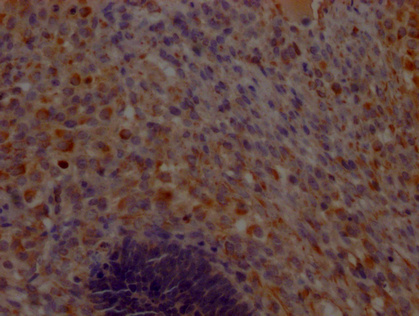

IHC image of CSB-PA861130LA01HU diluted at 1:200 and staining in paraffin-embedded human testis tissue performed on a Leica BondTM system. After dewaxing and hydration, antigen retrieval was mediated by high pressure in a citrate buffer (pH 6.0). Section was blocked with 10% normal goat serum 30min at RT. Then primary antibody (1% BSA) was incubated at 4°C overnight. The primary is detected by a Goat anti-rabbit polymer IgG labeled by HRP and visualized using 0.05% DAB.